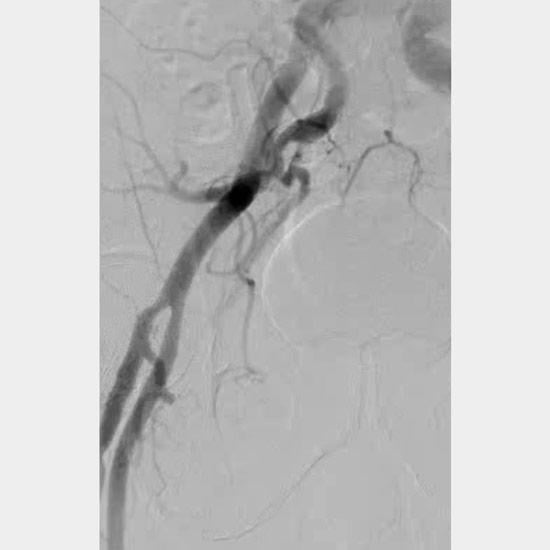

A 34-mm Evolut transcatheter aortic valve (TAV) (Medtronic) was deployed with a good result (Figure 1G). Closure of the femoral access site was uneventful (Figure 1H).

Figure 1H: Femoral angiogram demonstrated successful percutaneous closure.